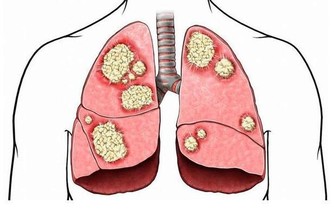

高血壓,是指以體循環動脈血壓(收縮壓和/或舒張壓)增高為主要特徵(收縮壓≥140毫米汞柱,舒張壓≥90毫米汞柱),可伴有心、腦、腎等器官的功能或器質性損害的臨床綜合徵。高血壓是最常見的慢性病,也是心腦血管病最主要的危險因素。

高血壓產生的原因有遺傳因素、精神和環境因素,生活習慣因素等,但是最常見的一個種原因是年齡原因。隨著年齡的不斷增長,40歲以上的中老年群體極易患高血壓,主要原因是人體血管內的各種代謝雜物擁堵與血管中,造成血液流量不穩,出現高血壓現象。作為一種常見的慢性疾病,高血壓可誘發冠心病、中風等多種致命的心腦血管疾病疾病,也被認為是中老年健康的“頭號殺手”,並且患上高血壓很難治愈,像不定時炸彈一樣伴隨終身。